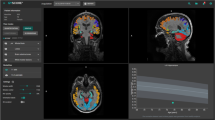

For clinical purposes and research projects in neurological disease, it is of interest to evaluate the performance and comparability of available sequences and software packages for brain volume assessment to determine whether they provide equivalent results. This study compares cross-sectional brain volume values derived from images obtained with MP-RAGE or MP2RAGE sequences, using SIENA/X, SPM, or MorphoBox.

MP-RAGE and MP2RAGE T1-weighted images were obtained from 24 healthy volunteers. Back-to-back scans were performed in 12 of them. Brain volumes, coefficients of variation, and concordance coefficients were determined.